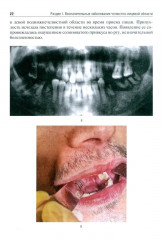

💳 Оплатить за товар можно при получении 🇰🇿 Есть бесплатная доставка по Казахстану от 1 дня 🎁 Копите бонусы с каждой покупки Учебное пособие подготовлено для студентов стоматологических факультетов медицинских вузов в соответствии с требованиями государственного образовательного стандарта и содержит сведения, необходимые для освоения в рамках учебной программы по специальности «Стоматология». В нем представлен набор иллюстрированных задач, в которых приведены наиболее часто встречающиеся клинические ситуации по основным разделам специальности: воспалительные заболевания челюстно-лицевой области (неспецифические и специфические); травматические повреждения и последствия травмы; онкологические заболевания; заболевания слюнных желез; заболевания височно-нижнечелюстного сустава; комплексное обследование и лечение пациентов с врожденными и приобретенными дефектами и деформациями мягких тканей и костей челюстно-лицевой области. Рассмотренные клинические ситуации помогут формированию у студентов профессиональных умений по диагностике и планированию комплексного лечения основных заболеваний челюстно-лицевой области. |